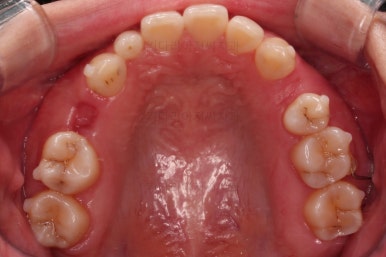

임플란트 보철까지 잘 세팅이 된 후 마무리 하게 되었습니다.

임플란트까지 잘 들어간 후 마무리 했고요.

결손공간 없이 상하좌우 모두 같은 갯수의 치아로 치료가 잘 종료되었습니다.

부산인비절라인 전후 비교해 볼게요.

매우 세심한 컨트롤로 입매는 매우 양호하게 잘 마무리가 되었습니다.

당연히 빈공간에 대한 처리도 잘 되었고요.

얼굴에 대한 중앙선도 잘 마무리 되었습니다.